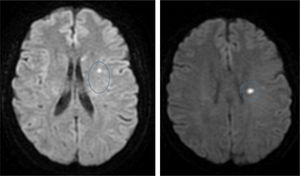

En la RM cerebral se evidenciaron unas lesiones isquémicas agudas/subagudas en el territorio de las arterias cerebral media y cerebral anterior izquierdas, con lo que la disección de ACI izquierda, mediante mecanismo embólico arterio-arterial provocó un ictus parcial multiterritorio paucisintomático desde el punto de vista neurológico (fig. 2).